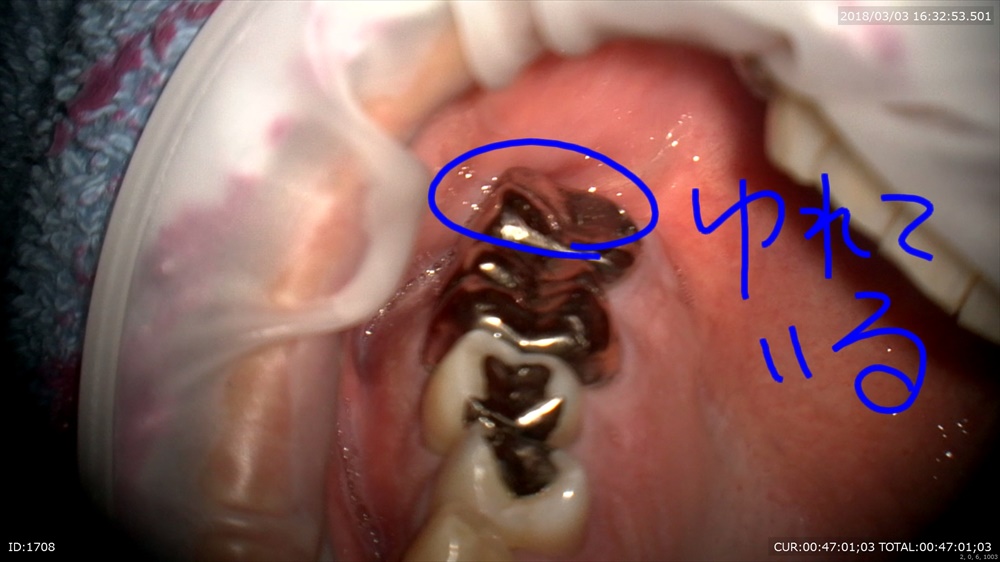

何かある。MB2がありました。

ここから膿がでてきた!!これも原因。マイクロスコープがないと見えませんでした。